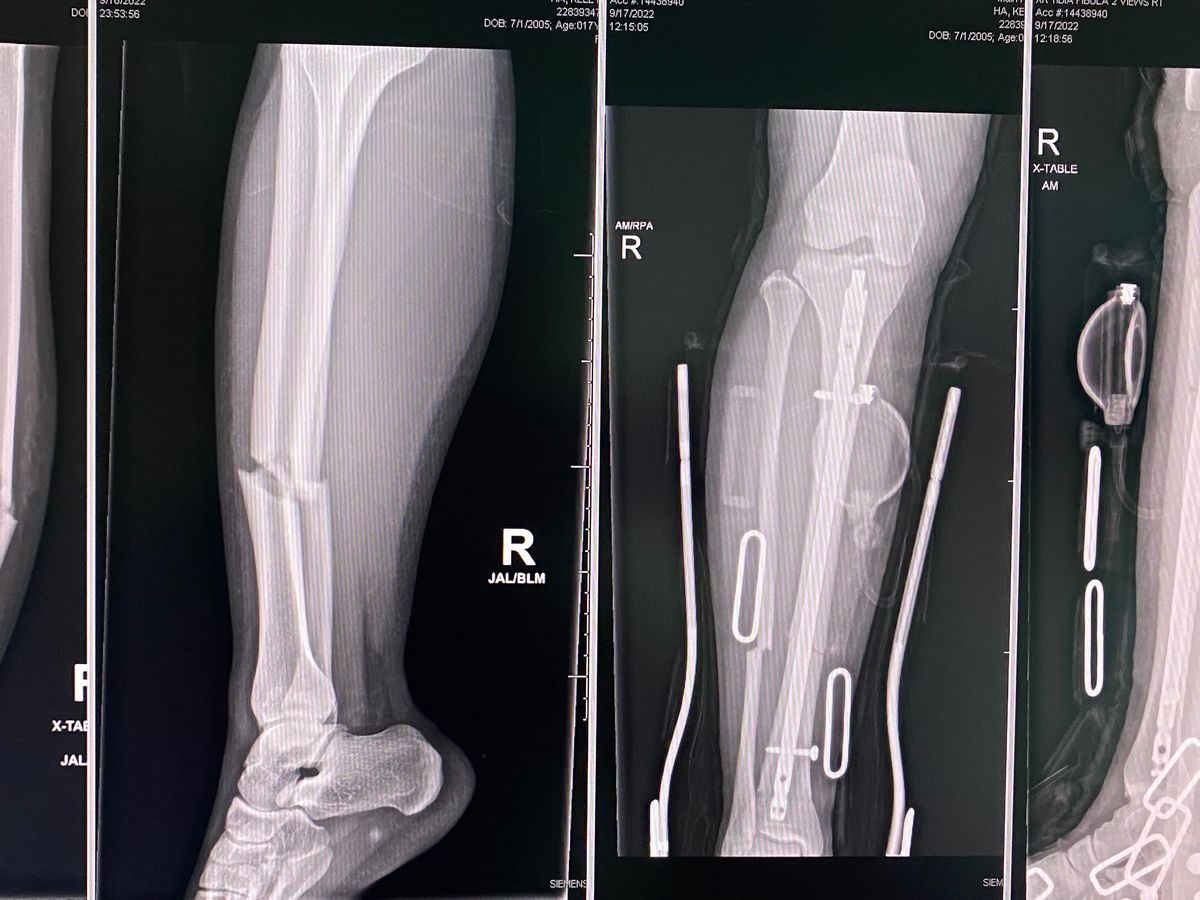

On September 17, Kelly was playing a volleyball tournament in Wendover. She was going up to block against a girl twice her height and size. When they both came down the girl stepped over the line under the net which caused her to step on Kelly’s foot causing her to land and break her tibial and fibula bone. The ambulance and firefighters were called and then was life flighted into the University of Utah. She had surgery September 18 at 7 am and had to have a rod and screwed placed in to stabilize the bone so that it may heal properly. Her recovery is going to be anywhere around 3-8 months.